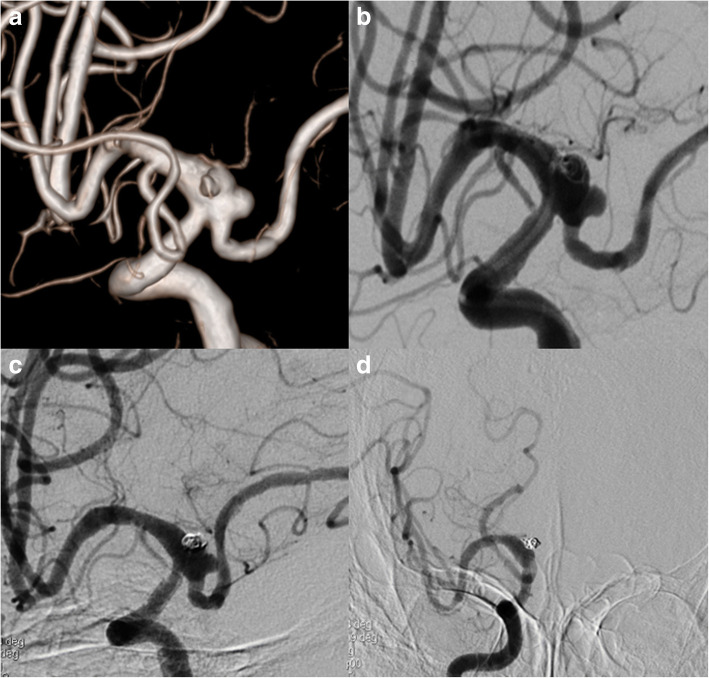

Fig. 1.

3D DSA image of Case NO. 1 before the treatment (a), immediate postoperative angiogram (b) and on follow-up (c), note that the right A1 was not patent, the distal part of right ACA was supplied by compensatory flow from the AComA (d)

This was a 61 years old female presented with a ruptured PCoA aneurysm which incorporated the origin of a right fetal PCA. The aneurysm was measured 3.0 mm*4.0 mm with a relative wide neck and two daughter aneurysms (Fig. 1a). We postponed the procedure 20 days after the onset of SAH to avoid the potential risks of dual antiplatelet therapy. The daughter aneurysm located superiorly was considered to be the rupture point, so we first loosely embolised it with three coils measured 2 mm*3 cm, 1.5 mm*2 cm, 2 mm*4 cm, then we deployed a 4.5 mm*20 mm PED from M1 segment to supraclinoidal segment of ICA covering the neck of the aneurysm (Fig. 1b). No further coiling of the aneurysm was performed in consideration of the future patency of fetal PCA. The follow up angiogram on 4 months demonstrated the patency of the fetal PCA and the aneurysm has slightly decreased in size (Fig. 1c), however there remained contrast agent filling in the aneurysm sac. Note that the right A1 is no longer patent and the patient was asymptomatic due to the compensatory flow from the AComA (Fig. 1d). So we discontinued the dual antiplatelet therapy and leave this patient on MRI follow up, we will not retreat the patient unless the patient will present with headache and enlargement of the aneurysm on MRI image.